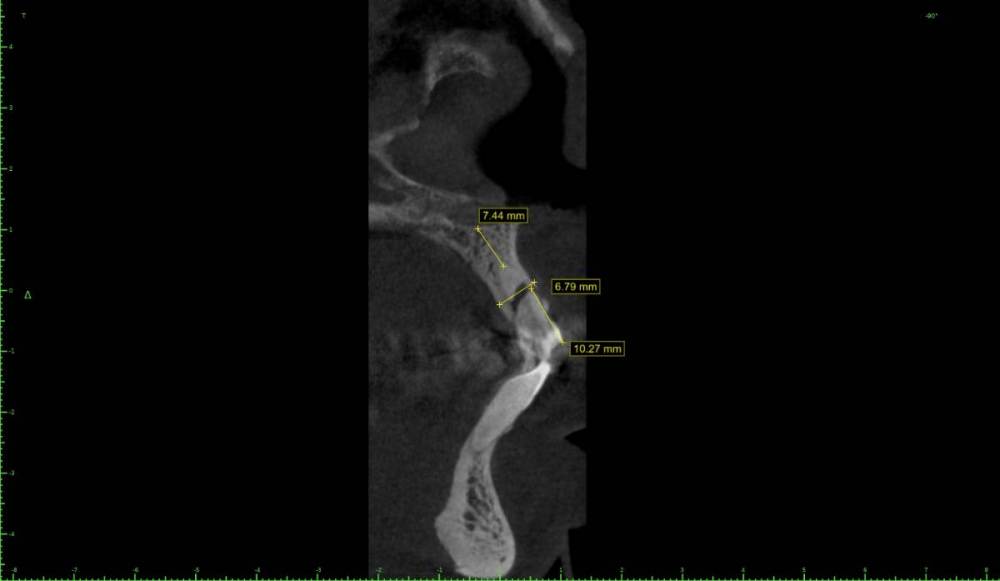

Женька Опубликовано 19 октября, 2021 Автор Поделиться Опубликовано 19 октября, 2021 @pit вот такой бугор у пациентки есть Ссылка на комментарий

pit Опубликовано 19 октября, 2021 Поделиться Опубликовано 19 октября, 2021 4 минуты назад, Женька сказал: @pit вот такой бугор у пациентки есть. Так это ж праздник какой-то))))))). Можно выполнить аля ИДР, забрать бугор трепаном. Просто, быстро и эффективно! 1 минуту назад, Женька сказал: @Irouil idr возможно провести на формирователе десны? Или обязательно нужно времянку поставить? Вообще не обязательно) 1 Ссылка на комментарий

Irouil Опубликовано 19 октября, 2021 Поделиться Опубликовано 19 октября, 2021 3 часа назад, Женька сказал: @Irouil idr возможно провести на формирователе десны? Или обязательно нужно времянку поставить? Имхо времянку лучше, будет герметичнее. Если я ставлю стандартные ФДМ, то аугментирую избыточно, «с запасом», да ещё и потом приходится это все «отжимать». Если правильно сделать временную коронку/иФДМ то вся эта запара не нужна. Почему вообще стоит такой выбор? Долотом бугор забирается удобно, а такой как на приведённых срезах - практически с закрытыми глазами. Ссылка на комментарий